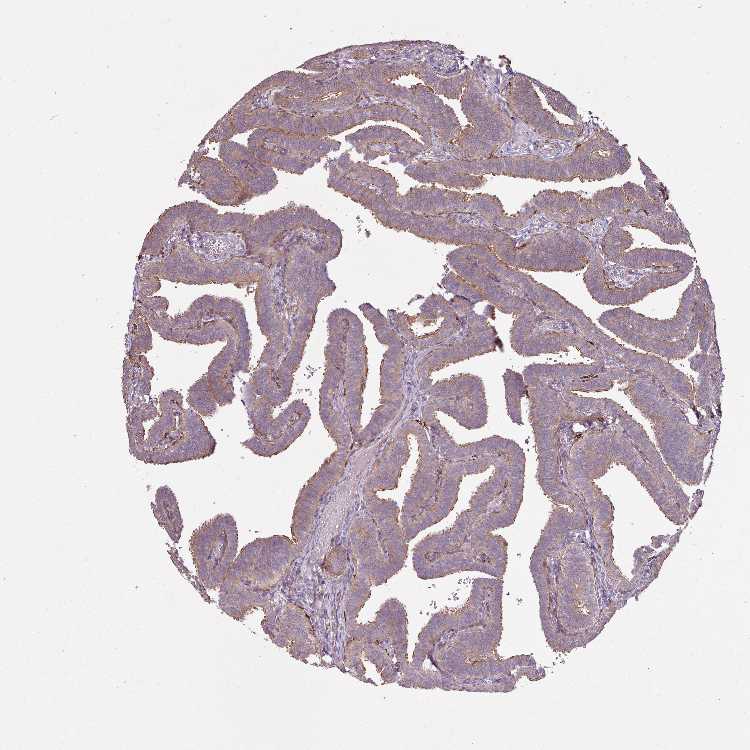

FALLOPIAN TUBE - Antibody stainingi

Antibody staining in the annotated cell types in the current human tissue is reported as not detected, low, medium, or high, based on conventional immunohistochemistry profiling in selected tissues. This score is based on the combination of the staining intensity and fraction of stained cells.

Each image is clickable and will lead to virtual microscopy that enables deeper exploration of all samples and also displays staining intensity scores, fraction scores and subcellular localization as well as patient and tissue information for each sample.

Antibody HPA052129

Glandular cells Medium